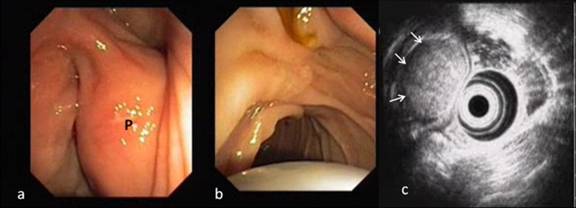

Figure 5. Repeat side view endoscopy along with EUS. a. Large polyp (P) in its original position within the proximal duodenum with a wide pedicle and normal overlying mucosa. b. The ampulla was normal and bile was seen passing through it. c. EUS showing well-defined echogenic mass confined to the submucosa (arrows) in the first part of the duodenum with no invasion beyond this layer. |

Abdominal ultrasonography showed a distended gallbladder without any calculi, prominent intrahepatic biliary radicals, a (10 mm) common bile duct dilated to the lower end with no calculi, prominent main pancreatic duct and a 2.8x1.9 cm hypoechoic mass near the distal end of the common bile duct. An abdominal computed tomography (CT) scan confirmed the dilatation of the common bile duct and the main pancreatic duct, and revealed an ill-defined hypodense mass 6.5x5.5 cm in size arising from the uncinate process of the pancreas (Figure 1). The mass involved the duodenum with an extension to the duodenojejunal flexure. The proximal duodenum was found to be dilated. The CT scan suggested the diagnosis of a pancreatic mass with duodenal infiltration. Upper gastrointestinal endoscopy was performed showing esophagitis and extraneous compression in the duodenal bulb. A side view endoscopy was performed and showed a long pedicle-like structure extending from the duodenal bulb into the distal duodenum along the medial wall of the second part of the duodenum (Figure 2). The distal end of this structure, the ampulla and the distal duodenal lumen could not be visualized. An attempt was made to pull the distal end of the structure using biopsy forceps but without success. Besides these findings, no ulcers, strictures or growths were found in the duodenum. In view of the endoscopic findings, the CT scan was again reviewed. The mass initially described as originating from the uncinate process was suspected to be intraluminal within the distal duodenum with a smooth outline at the distal end. However, this mass could not be defined as separate from the pancreas. In addition, a characteristic sign of “duodenal wall invagination” was observed in the dilated first part of the duodenum (Figure 3). Barium meal examination of the upper digestive tract showed a well defined smooth lobular filling defect in the dilated first part of the duodenum (Figure 4). Given the above findings, a duodenal polypoid mass of unknown nature was suspected. A side view endoscopy was repeated and endoscopic ultrasonography (EUS) was also performed. During this examination, a large polypoid mass with normal overlying mucosa was seen in the proximal duodenum (Figure 5a). The ampulla was seen as separate from the polyp and was found to be normal as was the visualized distal duodenum (Figure 5b). Endoscopic ultrasonography revealed a homogenous echogenic mass occupying the submucosa in the duodenal bulb with a normal pancreas which was not involved by the mass (Figure 5c). A biopsy taken from the polyp showed non-specific changes in the mucosa.

Preoperative endoscopy and biopsy may help in making a correct diagnosis but with limitations (72-89% sensitivity) [4] as these lesions are submucosal and may be missed by a mucosal pinch biopsy. Endoscopic ultrasound may also be helpful. On EUS, Brunner’s gland hamartoma is characterized by a heterogeneous solid and/or cystic or multicystic mass [25], or a homogenous echogenic mass located in the submucosa [26]. On barium examination of the upper digestive tract, these lesions produce a characteristic “cobblestone” appearance or a well defined filling defect [26]. Although intraoperative biopsy has a sensitivity of 83-92% [4], serious complications (e.g. pancreatitis, pancreatic fistula or bleeding) may occur in addition to the possibility of sampling error. However, major surgery, such as a pancreaticoduodenectomy, may be resorted to if there remains a strong suspicion of malignancy, even after an extensive work-up, provided such surgery is performed at a specialized center with low morbidity and mortality rates [4]. In our case, we were able to correctly rule out the pancreaticoduodenal malignancy by performing more extensive evaluation with a barium study, repeat endoscopy and endoscopic sonography.